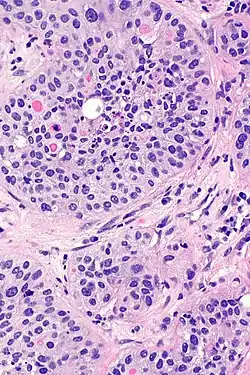

Rak urotelialny pęcherza moczowego

Mikroskopowo w utkaniu obecne są komórki tworzące gniazda, sznury komórek lub pojedyncze komórki pooddzielane desmoplastycznym podścieliskiem[76][78]. Możliwy jest bardziej rozlany wzór wzrostu nowotworu, w którym komórki tworzą arkusze, przy czym również w takim utkaniu spotyka się ogniskowo występujące gniazda komórek[78]. Komórki cechują się umiarkowaną do obfitej ilością amfofilnej lub eozynofilnej cytoplazmy i dużym hiperchromatycznym jądrem komórkowym. Jądra komórkowe wykazują znaczną pleomorficzność, nieregularne, kanciaste granice. Liczba i wygląd jąderek wykazuje znaczną zmienność. Gniazda komórek nowotworowych zwykle indukują reakcję desmoplastyczną podścieliska. Obecne są liczne figury mitotyczne i możliwa jest obecność nieprawidłowych figur mitotycznych. W podścielisku większości guzów jest obecny naciek limfocytów i komórek plazmatycznych, naciek najczęściej jest wyrażony ogniskowo od łagodnego do umiarkowanego stopnia, ale może być nasilony i rozlany[76][78]. Może być widoczna inwazja naczyń[78].